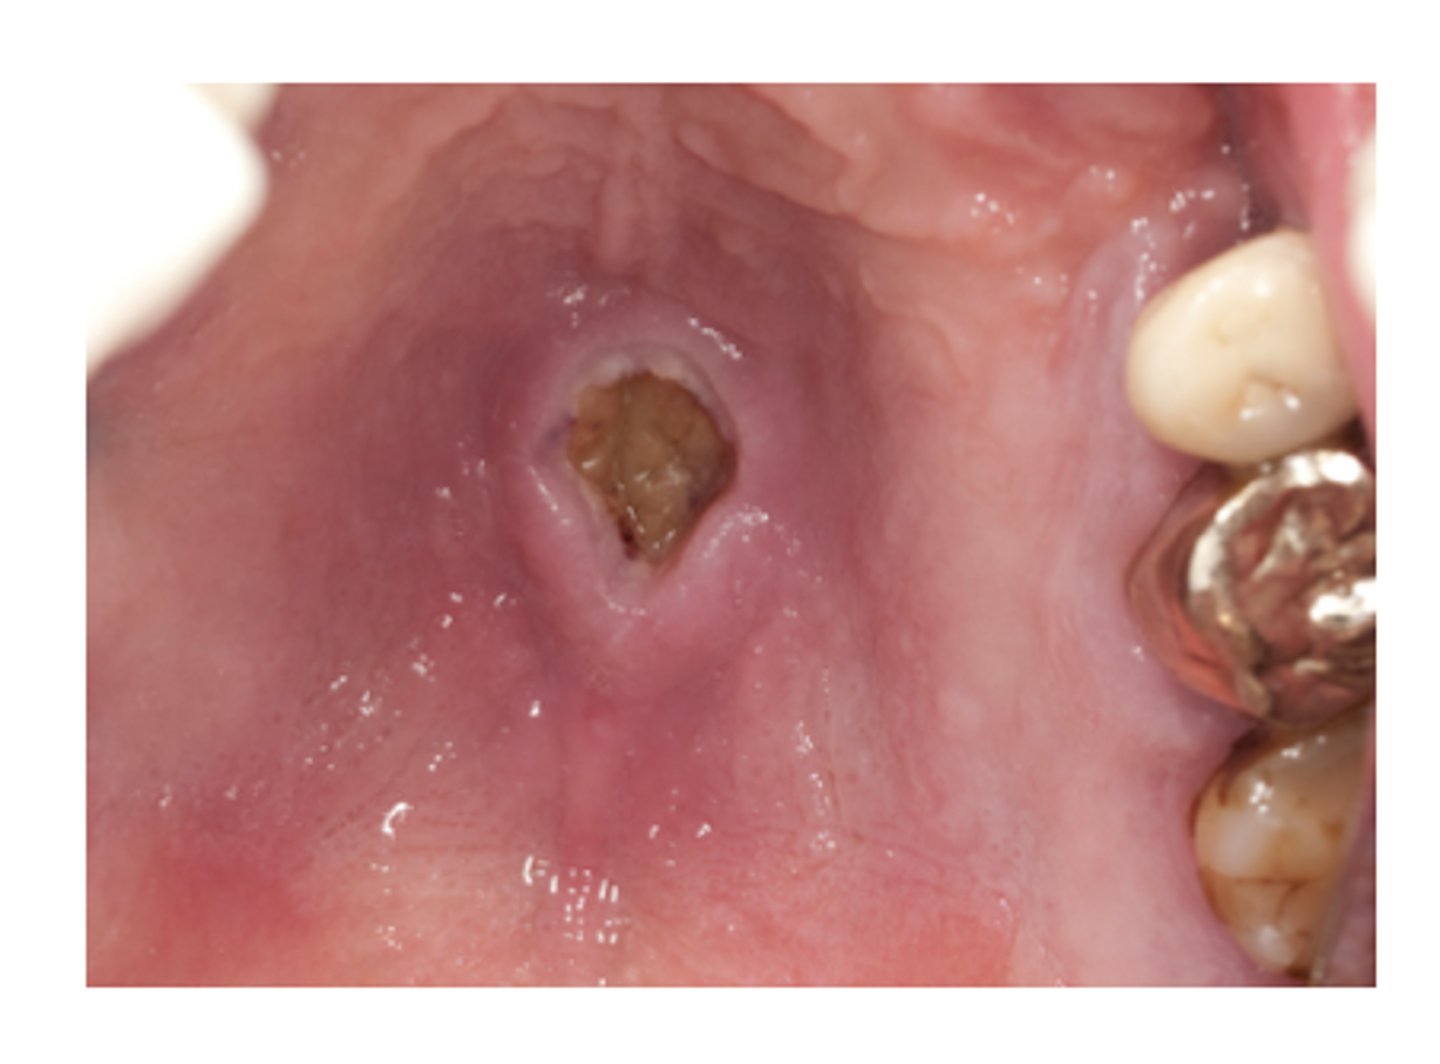

Necrotizing Sialometaplasia

Ischemia of the salivary glands of the hard palate, Often bilateral and symmetrical, starts out initially as a swelling

What condition can mimic squamous cell carcinoma?

Pseudoepitheliomatous hyperplasia, Coagulative necrosis of

the adjacent glands